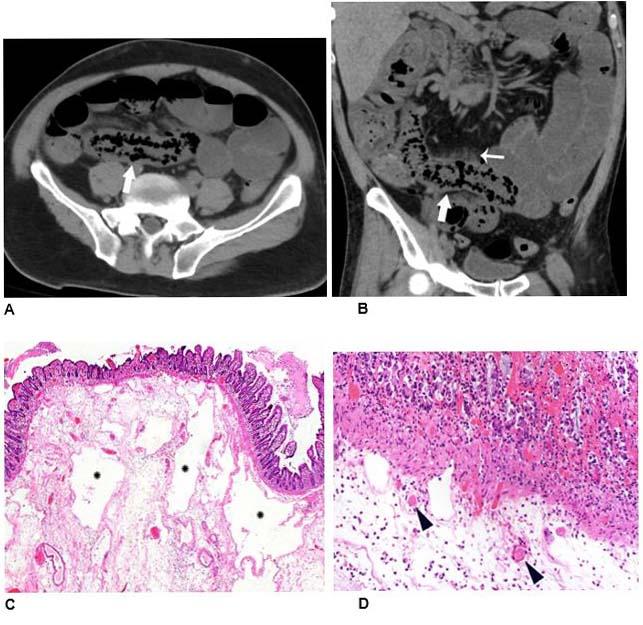

Records showed that 17% of patients had cross-sectional abdominal imaging, including 44 ultrasounds, 42 CT scans, and 1 MRI. Bowel abnormalities were seen on 31% of CT scans (3.2% of all patients) and were more frequent in intensive care unit (ICU) patients than other inpatients. Bowel findings included thickening and findings of ischemia such as pneumatosis (gas in the bowel wall) and portal venous gas. Surgical correlation in four patients revealed unusual yellow discoloration of bowel in three of the patients, and bowel infarction (dead bowel) in two patients.

In two patients who had bowel resection, pathology demonstrated ischemia with patchy necrosis (injury due to reduced arterial flow with patchy areas of cell death). Both had fibrin thrombi (blood clots) in submucosal arterioles (small arteries in the bowel wall), suggesting bowel ischemia in these patients might be caused by these small blood clots. Lung base findings led to a diagnosis of COVID-19 in one patient who presented with abdominal symptoms only. Of right upper quadrant ultrasounds, 87% were performed for liver laboratory findings, and 54% demonstrated a dilated sludge-filled gallbladder suggestive of cholestasis, or a decrease in bile flow.

"Some findings were typical of bowel ischemia, or dying bowel, and in those who had surgery we saw small vessel clots beside areas of dead bowel," Dr. Bhayana said. "Patients in the ICU can have bowel ischemia for other reasons, but we know COVID-19 can lead to clotting and small vessel injury, so bowel might also be affected by this."

According to the researchers, possible explanations for the spectrum of bowel findings in patients with COVID-19 include direct viral infection, small vessel thrombosis, or nonocclusive mesenteric ischemia. "ACE2 expression is most abundant in lung alveolar epithelial cells, enterocytes of the small intestine, and vascular endothelium suggesting that small bowel and vasculature may be susceptible to SARS-CoV-2 infection," they wrote.